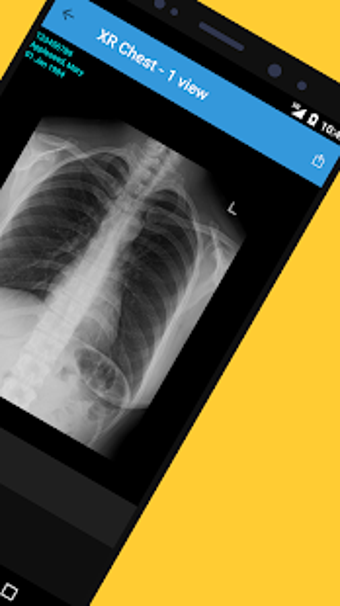

Met Affidea Connect Patient kunt u uw beeldvormingsresultaten bekijken, ze delen met uw zorgverleners en overal en altijd toegang krijgen. De app is gemakkelijk te gebruiken en u kunt er zonder moeite doorheen navigeren. U kunt ook eerdere beeldvormingsresultaten bekijken, waardoor het gemakkelijker wordt om uw voortgang te vergelijken en bij te houden. Over het algemeen is Affidea Connect Patient een geweldige app die u helpt om de controle te houden over uw gezondheidszorg en geïnformeerde beslissingen te nemen over uw gezondheid.